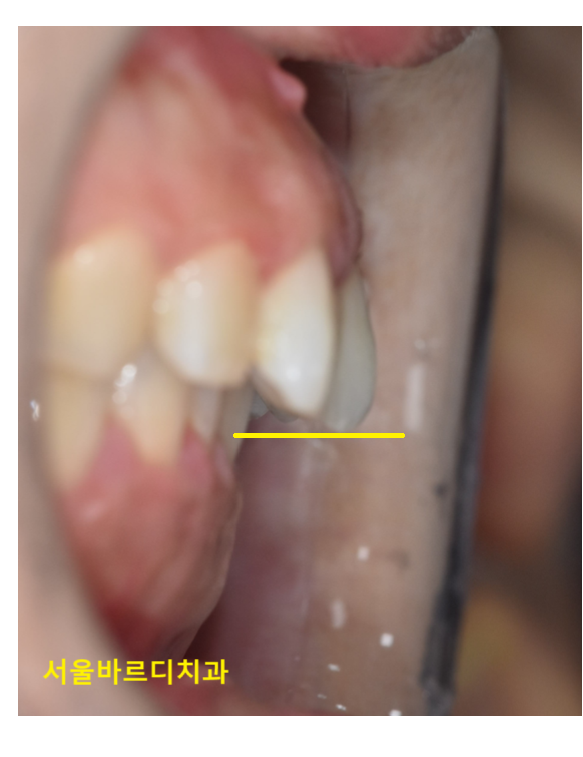

첫번째로 턱뼈의 성장 문제가 있습니다.

위턱과 아래턱의 성장 속도가 달라 교합이 어긋날 수 있습니다.

250430 턱 성장의 차이